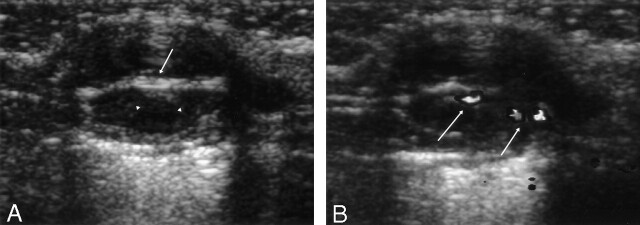

Fig 1.

Sonograms.

A, Gray-scale sonogram shows a well-defined 1.6 × 2-cm mass with posterior acoustic enhancement. An echogenic central septum (white arrow) and slightly low echoic peripheral thick wall (white arrowheads) are seen.

B, Color Doppler sonogram shows increased vascularity at the septal solid portion of the lesion (white arrows).

An 11-year-old girl was admitted to hospital because of a palpable mass in the left submental area. The mass was palpable 3 months before admission. Initial fine needle aspiration revealed some follicular epithelial cells with mild atypia and columnar cells and was presumed to be a thyroglossal duct cyst. Sonography showed a predominantly cystic mass and internal solid septa (Fig 1A). Color Doppler sonography showed increased vascularity around the solid septa (Fig 1B). The relationship between the mass and hyoid bone was not clearly demonstrated sonographically. The mass was thought to be an atypical lesion associated with thyroglossal duct remnant. Nonenhanced axial CT showed a well-defined mass with a central low-attenuation area (Fig 2A). The central portion was 20.2 H. There was no remarkable fat infiltration adjacent to the mass. Contrast-enhanced axial CT disclosed peripheral, enhancing mural nodules and septation that showed moderate contrast enhancement. The lesion abutted the hyoid bone partly at its upper medial aspect (Fig 2B). Contrast-enhanced coronal CT showed the mylohyoid muscle was compressed, and the boundary between the upper part of the mass and the mouth floor was indistinct (Fig 2C). No lymphadenopathy larger than 1 cm in its maximal diameter was seen. The CT finding was thought to be a predominantly cystic mass with a malignant component such as a carcinoma arising from thyroglossal duct remnant. The lesion was removed en bloc. On surgical field, some adhesion between the mass and the adjacent muscles were seen. Microscopic findings were consistent with classic biphasic synovial sarcoma (Fig 3A). Immunohistochemical staining revealed positive immunoreactivity to CD99, BCL2, and CK (AE1/AE3) antibodies (Fig 3B).